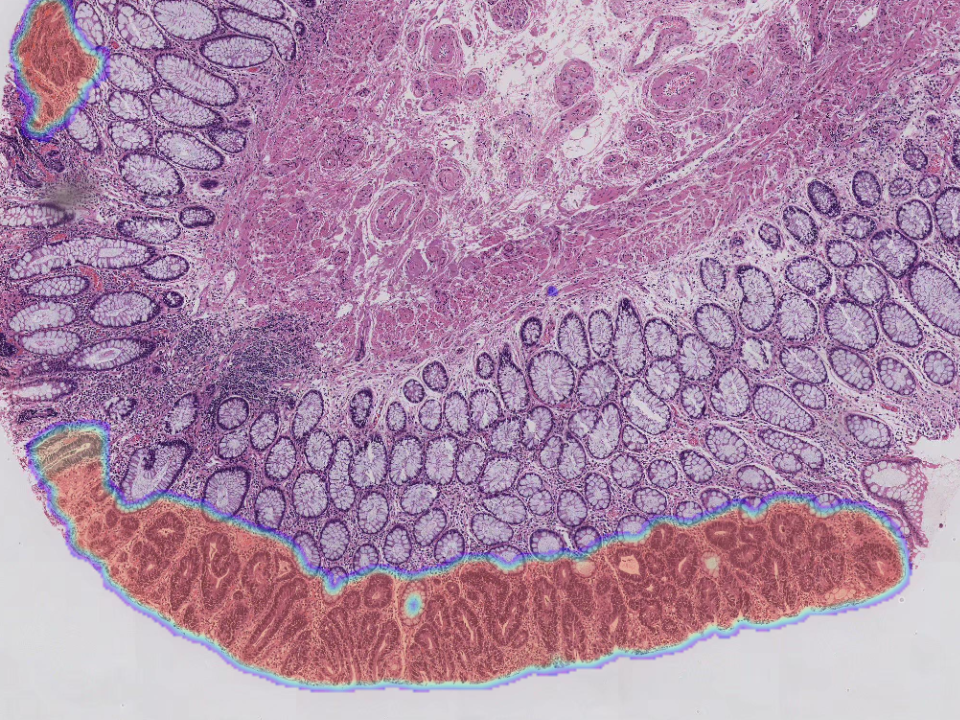

Intestinal Biopsy Assistant Diagnostic Module

Detection of small early lesion areas with high accuracy. Automatically recognize six lesion types,covering more than 95%of lesion types. Significantly shorten the diagnostic time and reduce workload. Combine pathology images,colonoscopy and disease history to improve diagnostic accuracy.

Intestinal Biopsy Assistant Diagnostic Module

Detection of small early lesion areas with high accuracy.

Automatically recognize six lesion types,covering more than 95%of lesion types.

Significantly shorten the diagnostic time and reduce workload.

Combine pathology images,colonoscopy and disease history to improve diagnostic accuracy.